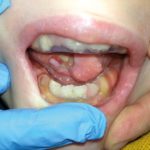

Impiego di gel piastrinico per la cura delle ulcere orali in pazienti affetti da...

Progressiva remissione delle ulcere a livello del cavo orale e della relativa sintomatologia dolorosa grazie all’utilizzo di un aggregato piastrinico con o senza biostimolazione laser. I risultati di un importante studio clinico realizzato presso la Dental School dell’Università di Torino.